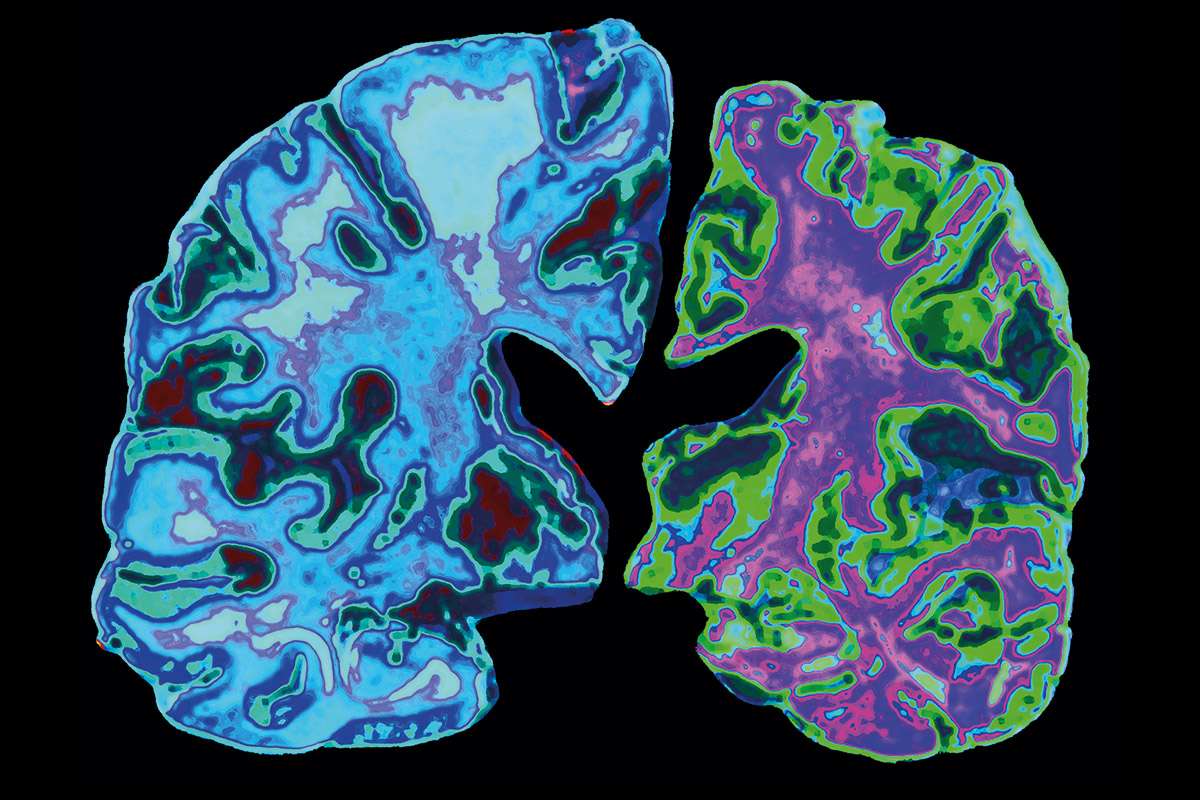

- في الواقع، جميع الأمراض الجسدية هي مرآة لصراعاتنا الداخلية ورغباتنا التي لا لبس فيها.

- يقول في كتابه “العلاج الكوانتي” عن المعدة السعيدة والحزينة وعن كلى غاضبة وعنق مخيف يشرح كيف تغمر طاقة عواطفنا كل عضو وخلية في جسمنا.